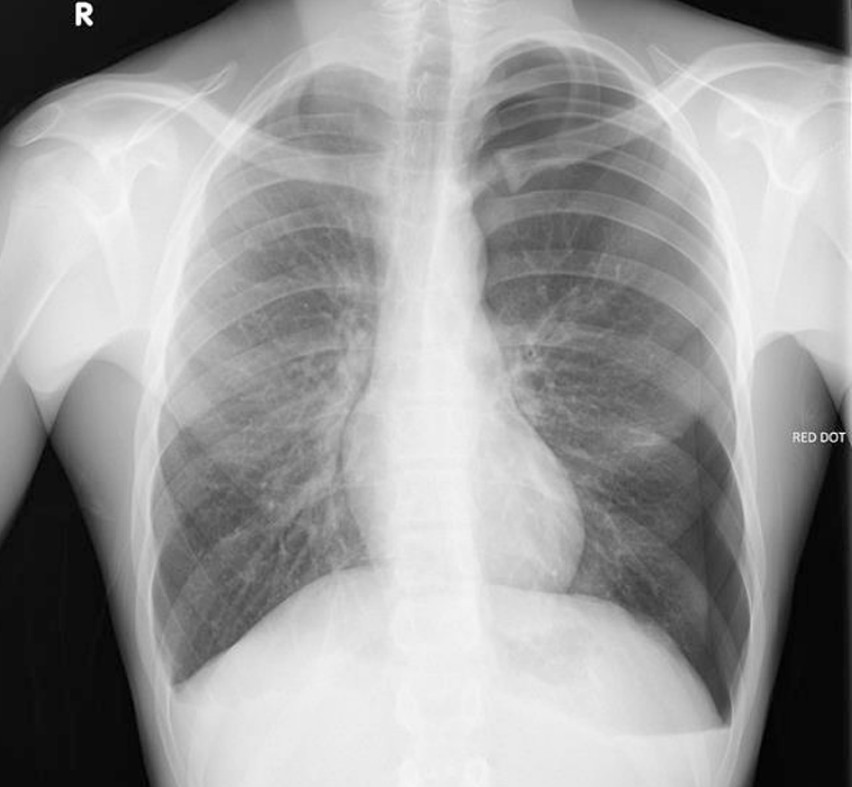

Penetrating chest trauma

A 35-year-old man presents following an industrial injury. His vital signs are currently stable.